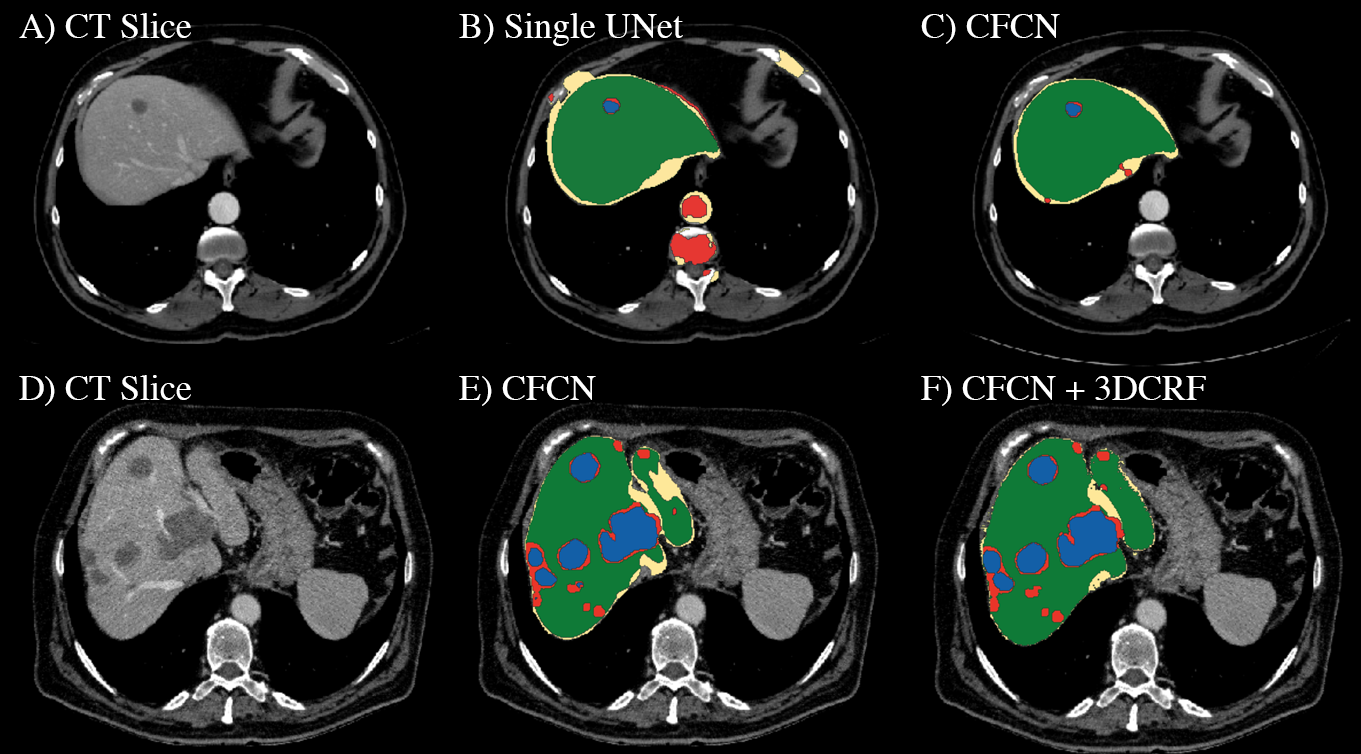

The qualitative results of the automatic segmentation are presented in figure 7. The complex and heterogeneous structure of the liver and all lesions were detected in the shown images. The cascaded FCN approach yielded an enhancement for lesions with respect to segmentation accuracy compared to a single FCN as can be seen in figure 7. In general, we observe significant666Two-sided paired t-test with p-value <41019absent4superscript1019<4\cdot 10^{-19} additional improvements for Dice overlaps of liver segmentations, from mean Dice 93.1%percent93.193.1\% to 94.3%percent94.394.3\% after applying the 3D CRF. For lesions we could achieve a Dice score of 56%percent5656\% at a standard deviation of 26%percent2626\% with a 2 fold cross-validation.

Figure 7: Automatic liver and lesion segmentation with cascaded fully convolutional networks (CFCN) and dense conditional random fields (CRF). Green depicts correctly predicted liver segmentation, yellow for liver false negative and false positive pixels (all wrong predictions), blue shows correctly predicted lesion segmentation and red lesion false negative and false positive pixels (all wrong predictions). In the first row, the false positive lesion prediction in B of a single U-Net as proposed by [18] were eliminated in C by CFCN as a result of restricting lesion segmentation to the liver ROI region. In the second row, applying the 3D CRF to CFCN in F increases both liver and lesion segmentation accuracy further, resulting in a lesion Dice score of 82.3%.